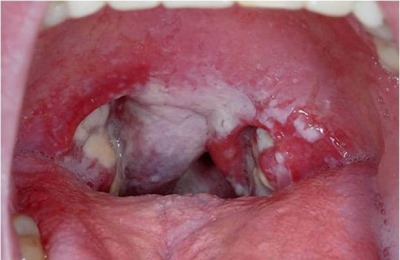

Ангина. Воспалительное поражение миндалин глоточного кольца – тонзиллит. При тонзиллите происходит увеличение миндалин, а также формировании на них налета.

При катаральной форме ангины такой налет белый или желтый, слабо выраженный, на фоне гиперемированных миндалин и небных дужек зева.

При фолликулярной форме тонзиллита, в миндалинах наблюдаются участки бело-желтого налета, который проникает уже в ткань лимфатического образования.

По сути, такой налет представляет собой гной, который сформировался из-за бактериального поражения слизистой и лимфоидной ткани.

При дальнейших более тяжелых формах ангины, уже формируются некротические изменения в тканях миндалин. Тогда визуально такой налет (белый или желтый), будет выглядеть в виде серо-черных участков нежизнеспособной ткани.

Молочница. Если слизистую оболочку ротовой полости, поразили грибки, чаще всего это грибки рода Candida, то во рту и горле формируется белый налет в виде творожистых масс.

Из-за этого симптома кандидоз и получил название молочница.